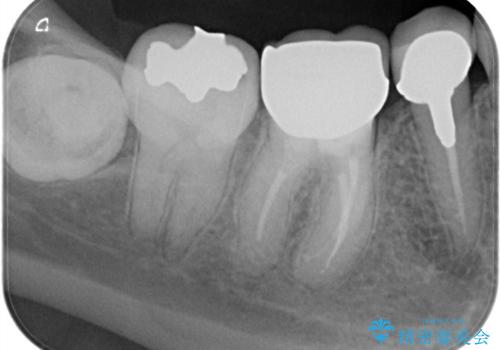

【外部吸収】根管治療、外科治療からのオールセラミッククラウン

- 歯肉の腫脹と被せ物の不適合を主訴に来院されました。

根管治療後、外部吸収を認めたため歯周外科を行ない歯冠修復を行なっております。

根管治療後には速やかに歯冠修復が必要です。